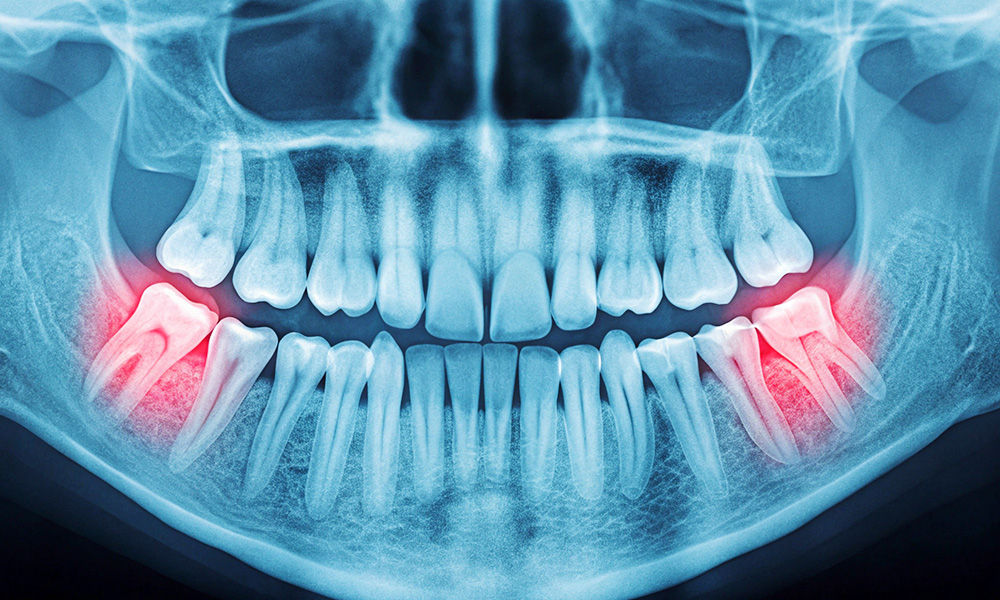

<下あごの親知らず>

下あごの親知らずも、上あごと同じで親知らずの頭が出ているかどうかで抜歯の難易度が変わります。上あごと比べて下あごの骨の方が硬いため上あごよりも抜きにくいです。

下あごの親知らずで注意しなければいけないのは親知らずの近くを通っている下歯槽神経と舌神経と呼ばれる2本の感覚神経です。

下あごの親知らずと神経の位置関係によっては注意しないと抜歯の際に神経の麻痺をおこすリスクがあります。

下あごの親知らずの方が上の親知らずと比べて抜きにくく抜歯後の腫れも出やすいです。抜歯後の腫れ等の不快症状を最小限にするよう当院では熟練の口腔外科医が親知らず抜歯を担当しています。